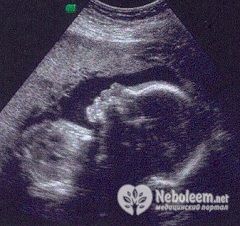

По УЗИ на 25 неделе беременности длина плода составляет около 32 см, масса до 700 г. Он уже достаточно большой, но все еще может изменить свое положение в матке. Движения и толчки будущего ребенка мать ощущает регулярно и отчетливо, у него есть собственный режим сна и бодрствования. Наиболее активным плод становится ближе к ночи.

На УЗИ в 25 недель беременности уже легко определяется пол будущего малыша.